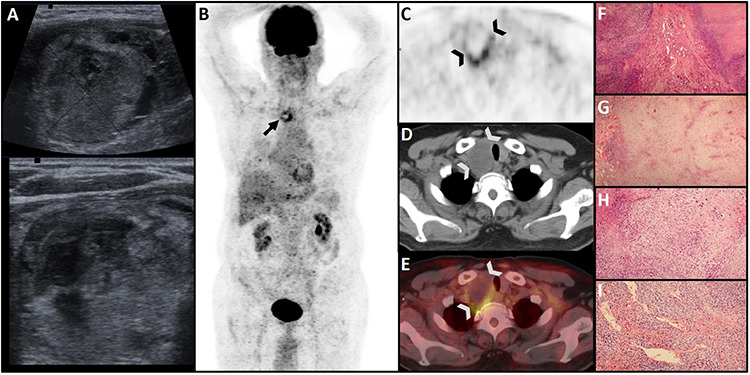

Pulmonary carcinosarcomas (PCS) are uncommon and aggressive malignant tumors with epithelial and mesenchymal components and have a worse prognosis than other non-small-cell lung cancers. Metastases of non-thyroidal malignancies to the thyroid are rare. We reported a unique case of isolated thyroidal metastasis of PCS and discussed 18F-fluorodeoxyglucose (18F-FDG) positivity in incidentally found thyroid nodules on 18F-FDG positron emission tomography scan.